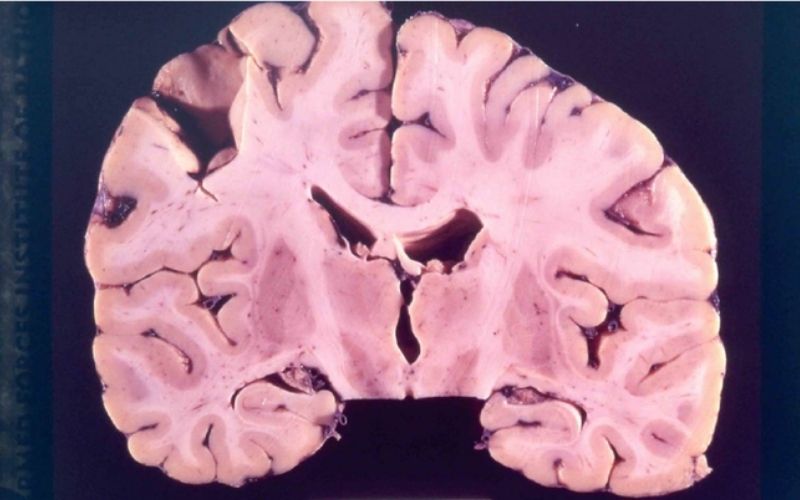

Bệnh Kuru là một rối loạn thần kinh hiếm gặp, do prion - một loại protein bất thường gây ra. Căn bệnh làm tổn thương não, tạo các lỗ rỗng như xốp và ảnh hưởng nghiêm trọng đến hệ thần kinh. Triệu chứng gồm run rẩy, khó đi lại, cười nói mất kiểm soát. Bệnh gần như luôn dẫn đến tử vong sau khi xuất hiện triệu chứng.

Khi prion tích tụ trong não, chúng gây thoái hóa mô thần kinh, dẫn đến các biểu hiện lâm sàng như run rẩy, mất điều hòa vận động và khó kiểm soát cử chỉ. Thời gian ủ bệnh Kuru kéo dài hàng thập kỷ, khó nhận biết sớm. Khi triệu chứng xuất hiện, tiến triển bệnh nhanh chóng và thường dẫn đến tử vong trong vòng 1 - 2 năm.